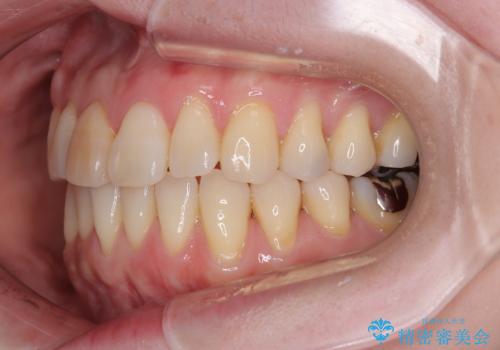

前歯のデコボコをインビザライン・モデレートで矯正治療

- 上下前歯のデコボコを気にして来院された患者様です。

安価なインビザラインパッケージを用いての治療を希望されており、デコボコの程度が中等度であったため、インビザライン・モデレートを用いて矯正治療を行うこととしました。